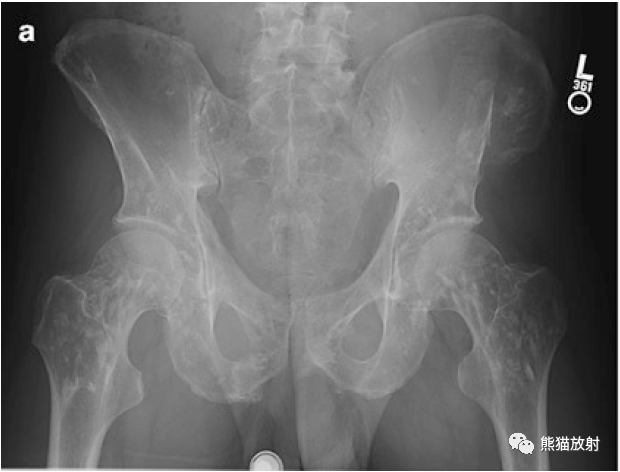

病史58岁男性,车祸后左侧骨盆疼痛。(A 58-year-old man with left sided pelvic pain following car accident.)

影像学表现股骨和骨盆骨可见多发小圆形硬化灶,X线片(a)和 CT图像(b)上都可见到左侧髂骨翼骨折。There are numerous small round sclerotic foci in the femurs and pelvic bones. Fracture of the left upper iliac wing is seen on both the radiograph (a) and CT image (b).

讨论骨斑点症的硬化灶通常小于广泛成骨性转移瘤或结节性硬化症的病灶。The sclerotic foci in osteopoikilosis are typically smaller that those seen with diffuse osteoblastic metastases or tuberous sclerosis.

• 是一种以关节周围骨性区域的多发小硬化灶(骨岛)为特点的硬化性骨发育不良。Sclerosing bone dysplasia characterized by numerous small sclerotic foci (bone islands) in periarticular osseous regions.

• 骨盆是最常见的受累部位。Pelvic bones are the most common site of involvement.